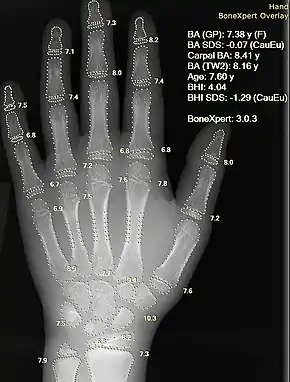

The most commonly used method is based on a single x-ray of the left hand, fingers, and wrist. A hand is easily x-rayed with minimal radiation [1] and shows many bones in a single view.[2] The bones in the x-ray are compared to the bones of a standard atlas, usually "Greulich and Pyle".[3][4]

Bone age rating is a procedure well-suited for automation by computer. The main advantage is the elimination of the variability of rating between different human raters. The BoneXpert method is the most prominent example of a completely automated method.[8]